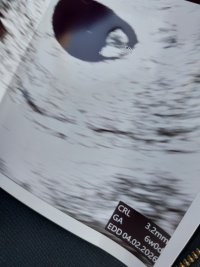

Varhaisultra

15.6 Vuorenpeikko 5+4

16.6 Macademia 6+5

16.6. Pöllöliini 7+1

17.6 Pikkukarhu 6+5, Mökkimakkara 7+3

18.6. Taikaiina 6+5

18.6. Elea 6+5

18.6. Elmatutu 6+5

19.6. perhonen_ 6+3

24.6. Lucky95 7+5

24.6. Muruli1985 7+5

26.6. ISLI 7+4

27.6. Tyrnimarja 6+6

28.6. Yhteistäykköstä 8+0

30.6 opahc 8+5

3.7. rihkis 8+2

8.7. Untuvapilvi 8+5

8.7. Pingviiniemo 8+2